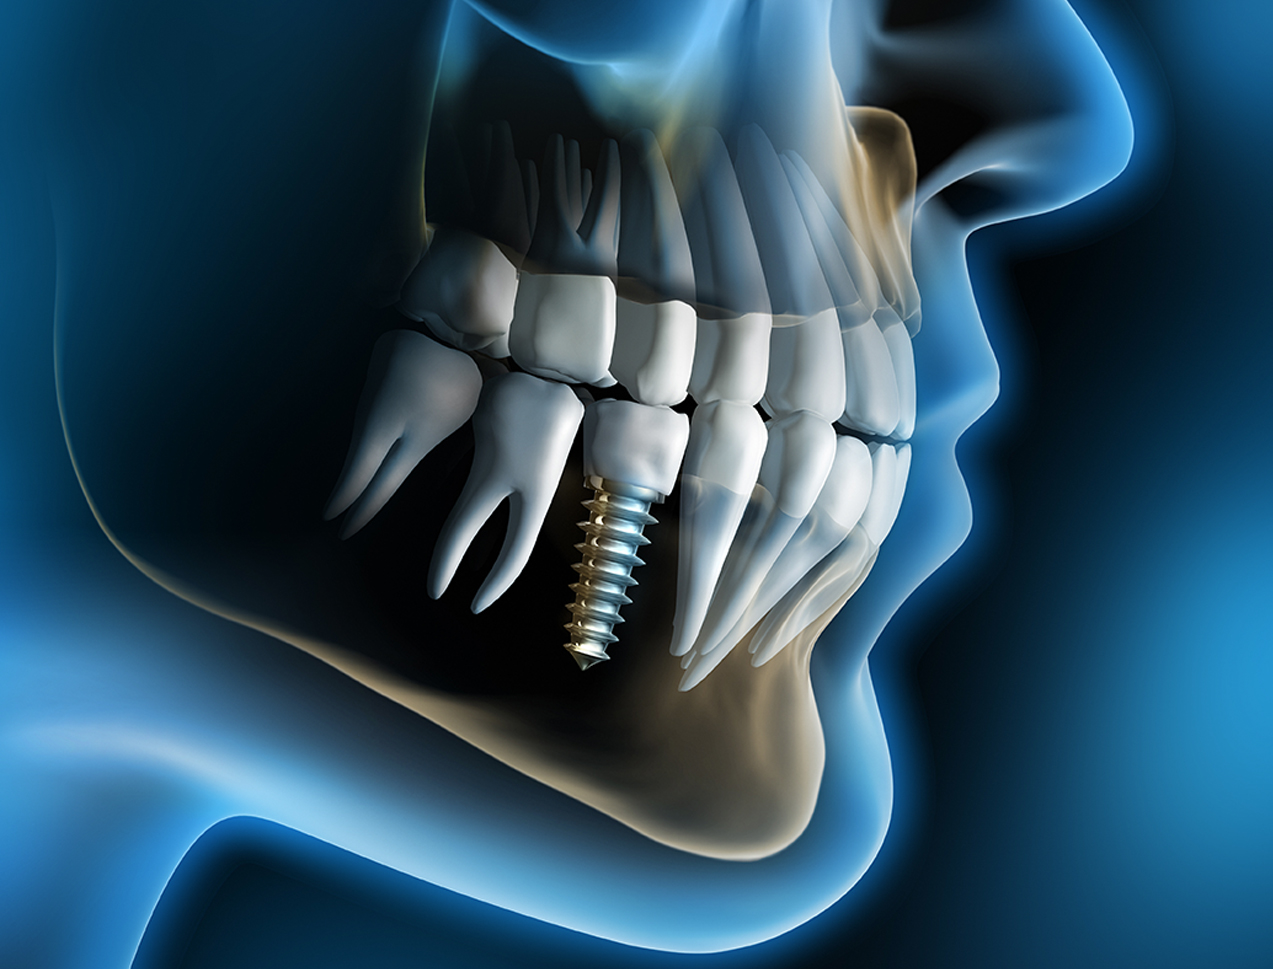

Implante Dental

Soluções seguras e duradouras para dentes perdidos